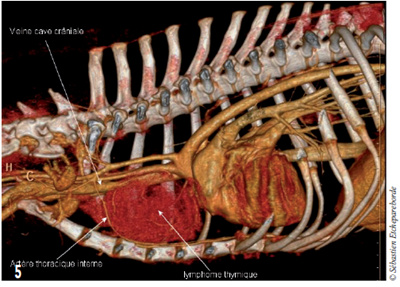

photo 5

On distingue nettement l’artère thoracique interne gauche prise dans la masse.

Un scanner est réalisé pour déterminer le caractère envahissant ou non de la masse. La masse fait 9 cm de diamètre.

Les vaisseaux sanguins dans le médiastin crânial (veine cave crâniale, carotides communes) semblent être repoussés

par la masse mais pas envahis. L’artère et veine thoracique interne gauche passent à travers la masse.

Aucune lymphadenopathie n’est visible. Il n’y a pas de métastases pulmonaires visibles.